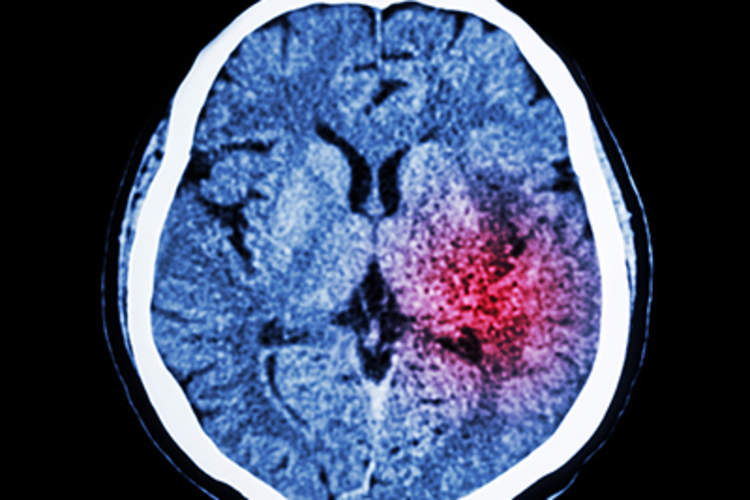

中风双打痴呆症的风险,大量研究发现

在调整了老年痴呆症的危险因素后,谁已经有中风的人的两倍,可能发展为痴呆,根据研究,涉及320万人。